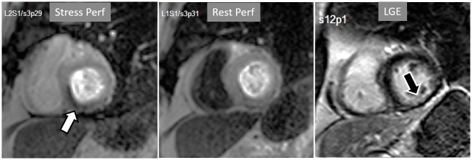

The presence of inducible residual peri-infarction ischemia in a territory with a previous MI has been addressed by the consideration of the extension of a stress perfusion defect in comparison with that of the LGE. Those defects with equal size on both sequences would be labelled as “fixed” (Fig. 16), while those perfusion defects exceeding the area of MI would be considered as “partially reversible” (Fig. 17), independently of rest perfusion studies. The diagnostic performance of the latter finding for the diagnosis of a residual significant stenosis in the infarct-related artery has been found to be adequate, though a good deal of cases with apparently fixed defects had also significantly obstructed arteries [46].

Fig. 16.Stress/Rest perfusion in chronic myocardial infarction. Perfusion defect during stress (performed in first place) (black arrow), not present at rest, matching the area of LGE (white arrow) in a case of large anterior subendocardial MI.

Fig. 17.Stress/Rest perfusion in chronic myocardial infarction. Perfusion defect during stress (performed in first place) (white arrow), not present at rest, fairly larger than the region of LGE (black arrow) in a patient with a subendocardial inferior MI.

When considering both, the variability of rest perfusion in the presence of previous MI, and the rather low sensitivity of partially reversible defects, the interest in knowing the actual extension of fixed defects emerges. An option to address the issue is to invert the order of perfusion studies in patients with previous MI, performing the rest study first. This allows for a reliable delineation of the fixed defect that can be easily subtracted from the inducible one, when present (Fig. 18). Moreover, in the case of patients with advanced, severe CAD, in whom a combination of infarcted regions and underperfused territories can be expected, a basal rest perfusion study followed by the stress one is even more helpful (Fig. 19). Certainly, the presence of CA in an area of MI after the first rest perfusion study may contaminate the SI of the second one, but this does not preclude the detection, or exclusion, of newly induced defects (Fig. 20).

Fig. 18.Rest/Stress perfusion in chronic myocardial infarction. Patient with previous myocardial necrosis involving most of the LV segments, mainly subendocardial in the anterior and septal regions, and transmural in the lateral wall, as shown in the LGE images (upper panel). The rest perfusion study, performed in first place (middle panel), shows a diffuse subendocardial defect, while, at a subsequent stress study (lower panel), a fair increase in transmurality and extension of the antero-septal defect is seen (arrows) indicating peri-infarction ischemia, while the lateral one remains unchanged. Note the lack of interference of the previous dose of CA on the tissue contrast of the stress study.